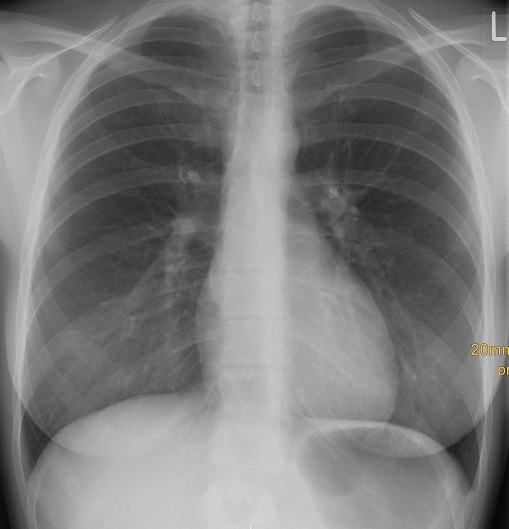

Dennoch werden auch heutzutage die meisten radiologischen Untersuchungen in Form der konventionellen Röntgenaufnahme, z.B. der Lunge oder eines Knochens angefertigt. Für viele Fragestellungen, z.B. nach einer Lungenentzündung oder einem Knochenbruch reicht dies auch heute im 21. Jahrhundert noch aus.

Röntgenthorax a.p. Normalbefund